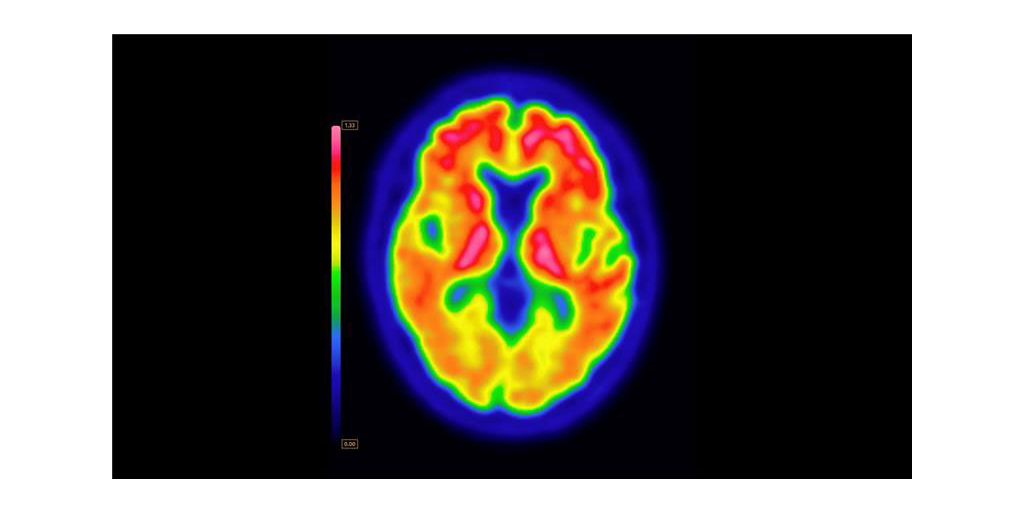

ARLINGTON HEIGHTS, Ill.–(BUSINESS WIRE)–GE HealthCare (Nasdaq: GEHC) today announced that the U.S. Food and Drug Administration (FDA) has approved an updated label for its positron emission tomography (PET) imaging agent VizamylTM (flutemetamol F 18 injection) for beta-amyloid detection. The revised label, effective immediately, expands the indications for use, enables quantitative analysis of Vizamyl scans, and removes significant previous limitations such as monitoring patient response to anti-amyloid therapy.

Up to now, amyloid diagnostics such as Vizamyl have been used to provide a visual assessment of amyloid plaque accumulation in the brain. With quantification now added to the label, clinicians can reach a more objective assessment, using software that enables a calculation of amyloid load, with published research demonstrating that quantification improves diagnostic confidence and consistency among readers1,2,3. In addition, with the removal of a limitation of use for monitoring therapy effectiveness, Vizamyl can also now be used to assess whether the level of amyloid plaques has been reduced sufficiently for the therapy to potentially be stopped.